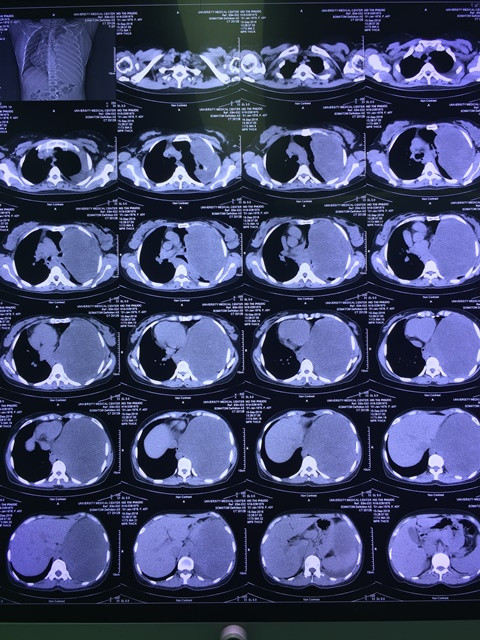

Kết quả siêu âm cho thấy có bất thường trong lồng ngực bệnh nhân. Chị P. tiếp tục được chụp CT và bác sĩ phát hiện khối u khổng lồ chiếm gần hết khoang lồng ngực bên trái. Khối u lớn đến nỗi đè xẹp hoàn toàn phổi trái, đường thở bị xô lệch và thậm chí đẩy quả tim lệch sang ngực phải.

Hình chụp CT khối u khổng lồ choán hết lồng ngực bệnh nhân. Ảnh do bệnh viện cung cấp.